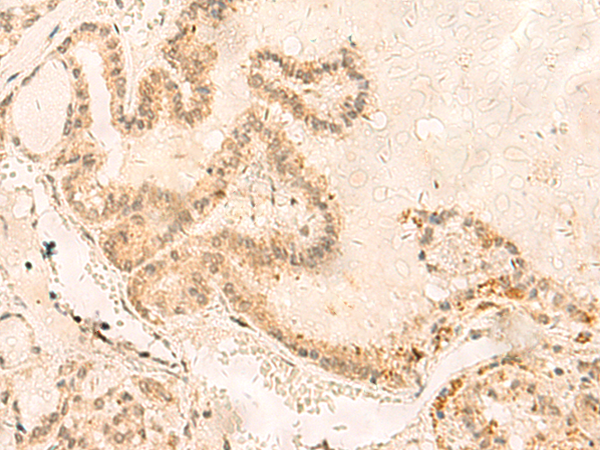

分类: 科研抗体货号: P06696别名: SS1; DRB1; HLA-DRB; HLA-DR1B应用: IHC反应种属: Human